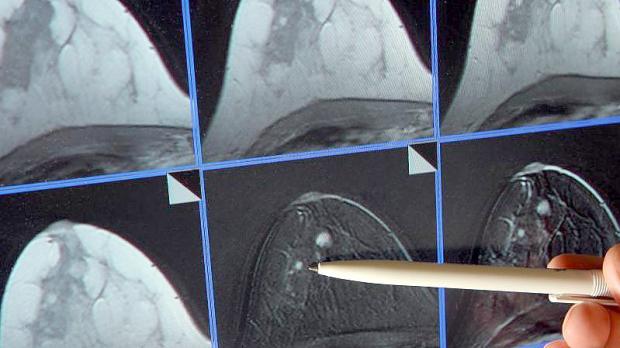

Immer wieder kommt es in der EU zu Engpässen bei Medikamenten. (Archivbild) Foto: Jan Woitas